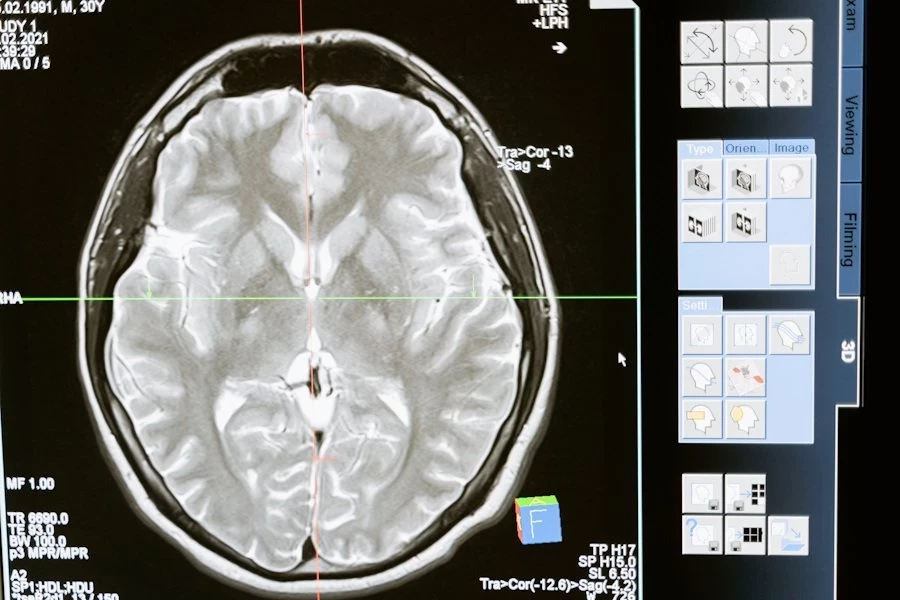

Загадочная болезнь мозга в Канаде: скрытая эпидемия или заговор

Премьер провинции Нью-Брансуик Сьюзан Холт обратилась к Агентству общественного здравоохранения Канады с просьбой помочь в расследовании таинственного заболевания мозга, поражающего жителей региона. Холт подчеркнула, что количество пациентов, страдающих от недуга, уже зашкаливает, а причины болезни до сих пор остаются загадкой.

Ситуация усугубилась после заявления одного из ведущих канадских ученых Майкла Култхарта, который сообщил, что ему запретили продолжать исследования болезни. Култхарт предполагает, что основным триггером могут быть факторы окружающей среды или их комбинация, вызывающие цепочку нейродегенеративных синдромов, подобных болезни Альцгеймера и болезни Паркинсона. Он подчеркнул, что данное заболевание не вписывается в стандартные диагностические рамки, что позволяет политикам избегать обсуждения проблемы и ограничивать доступ ученых к исследованиям.

Другой федеральный ученый поддержал его мнение, сообщив, что от загадочной болезни уже пострадали 350 человек. Это вызывает серьёзные опасения, так как распространение болезни приобретает характер эпидемии.